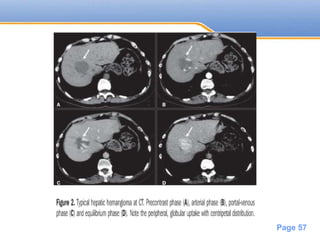

Pre contrast Arterial Phase Portal venous

phase

Delayed

Haemangioma Low attenuation Peripheral puddles Partial Fill in Complete fill in

Page 57

Powerpoint Templates